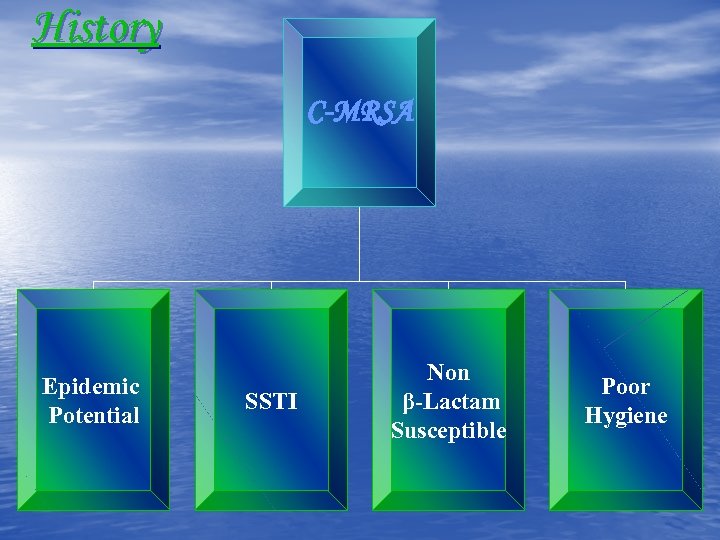

History C-MRSA Epidemic Potential SSTI Non β-Lactam Susceptible Poor Hygiene

History C-MRSA Epidemic Potential SSTI Non β-Lactam Susceptible Poor Hygiene